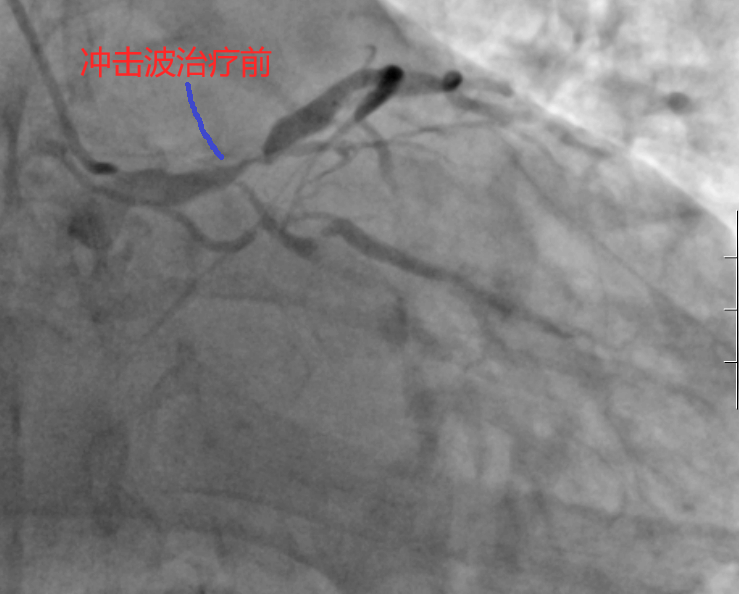

面对患者及其家属再次拒绝冠脉搭桥手术,并强烈要求微创介入治疗,九江学院第二附属医院心血管内科团队进行了缜密的术前讨论。考虑到患者左主干、前降支开口及近段存在重度狭窄且钙化严重,普通球囊扩张可能不能完全预处理狭窄病变,团队最终决定采取冲击波球囊扩张技术。经过充分的术前准备,手术在主动脉球囊反搏(IABP)支持下顺利进行。术中,医生们精准运用3.25X12mm冲击波球囊,在前降支近端及左主干分别进行了数次冲击波治疗,有效处理了钙化病变。最终,成功植入1枚支架,解决了患者的病痛。